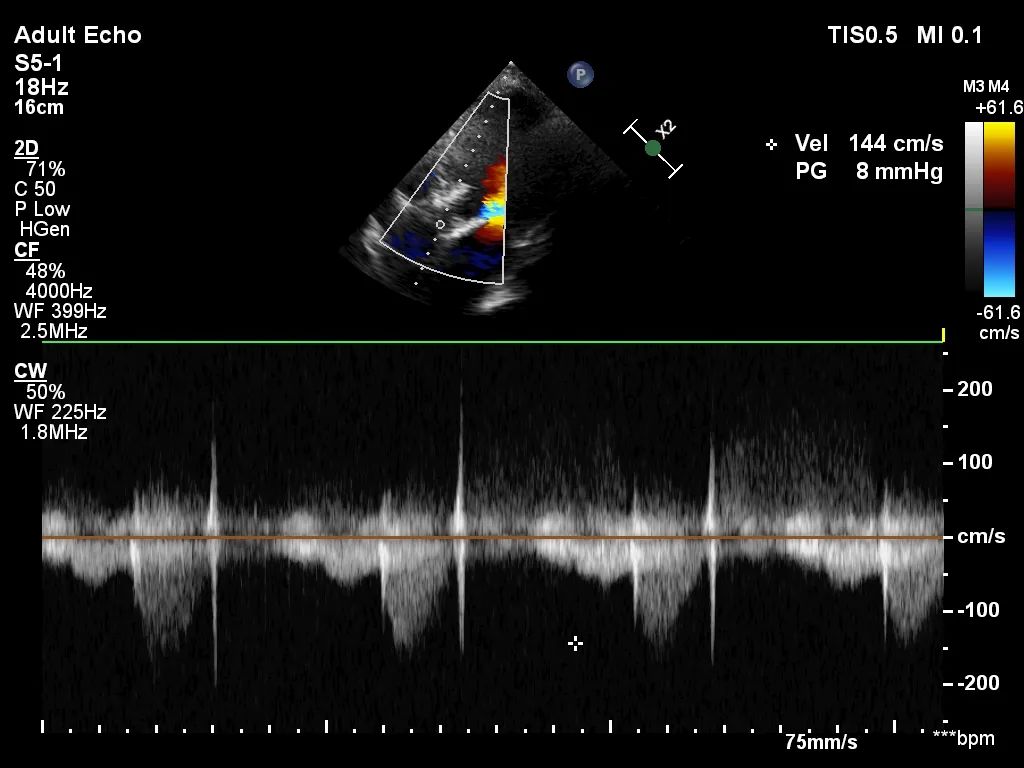

患者为83岁老年女性,主因“发作性胸闷胸痛10余年,加重1周”入院。患者病史明确,10余年来于多家医院诊断为“心功能不全”,予以保守治疗。1周前患者胸闷、胸痛加重,伴呼吸困难,活动后加重,夜间不能平卧。遂来我院就医,急诊心电图示“窦性心律”;胸部CT示“双肺散在炎症灶、心脏增大、肺动脉干增粗、双侧少量胸腔积液”;超声示“升主动脉硬化、主动脉瓣狭窄(重度)、主动脉瓣反流(中度)、二尖瓣反流(中度)。左室舒张末内径62mm、左房内径41mm、室间隔厚度9mm、主动脉瓣峰值压差56mmHg、LVEF 51%”。

8. 扩张后跨瓣压差降至8mmHg,造影示轻微瓣周漏,患者血流动力学指标改善明显,手术圆满成功。

• 在术前评估阶段,首先通过心电图及超声探查,对患者心力储备、心脏电生理状况有了一个基本的把握,明确了患者自身的心力储备情况。之后的CTA评估,通过瓣环上平面测量,提示了瓣叶钙化轻微,主动脉根部锚定力较弱。于术前明确了瓣中瓣发生可能性,为术中的快速决策提供了可能。